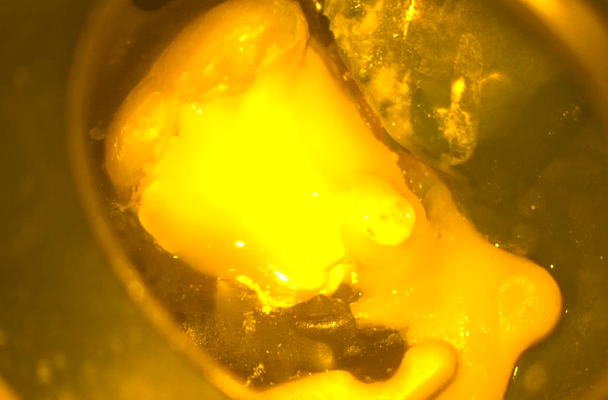

写真はすべてミラー像です。上顎左側側切歯遠心面の大きな虫歯です。エキスカで丁寧に軟化象牙質を除去していくと、歯髄腔まで本当に皮一枚になりました。血流が見えるようです。エキスカから伝わる組織の硬軟の感覚と対物-接眼レンズからの像が ”皮一枚”を達成できたと思います。皮一枚ですが、硬組織は残っていますので、ティース・プライマーを塗布し、スーパーボンド・ラジオオペークとバルクベースにて覆髄をしました。もちろん、1ケ月後の歯髄診でも陽性反応を示し、歯髄は生きています。

メタルインレー下にはレジンの覆髄が施されていましたが、接着しておらず、ポロリと取れました。これが、2次齲蝕(治療後の虫歯の再発)の原因です。多量の軟化象牙質(虫歯)を除去していくと、歯髄腔(神経と血管が入っている部屋)まで紙一枚。うっすら赤い血流も確認できます。齲蝕除去中に口蓋側の咬頭が破折しましたので、グラスファイバーポストによって、生活歯の支台築造。神経も取らずに残せる歯は、本当に多くあります。